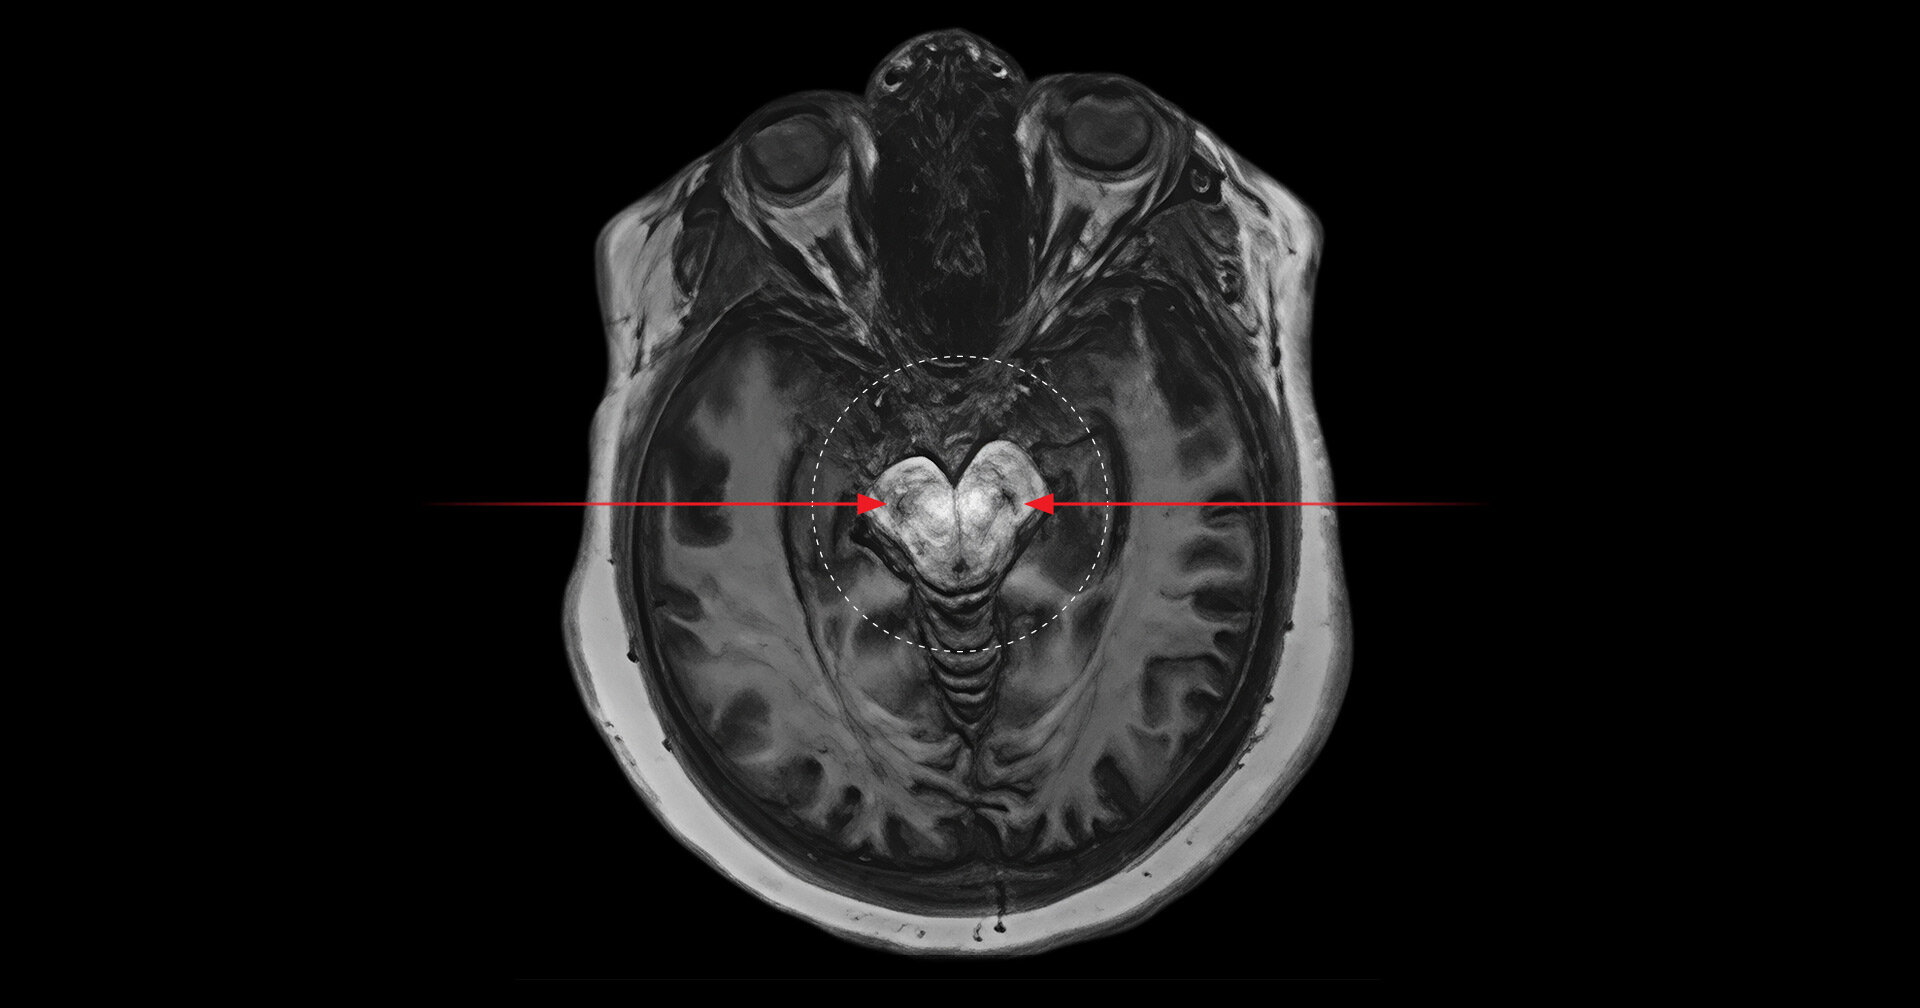

The real innovation lay in the imaging technique used: neuromelanin-sensitive magnetic resonance imaging (MRI). This non-invasive approach enables researchers to measure neuromelanin, a dark pigment that accumulates in the brain over time as a byproduct of dopamine metabolism.

“When there’s too much dopamine being produced, it leaves behind more neuromelanin,” explained Palaniyappan. “And that shows up as darker spots on the scans. In people who use cannabis excessively, those spots are darker than expected for their age—sometimes showing levels of pigment someone 10 years older would have.”

These “black spots” were especially concentrated in two areas of the midbrain—the substantia nigra and the ventral tegmental area (VTA)—regions intimately involved in the brain’s dopamine system and heavily implicated in psychotic disorders.